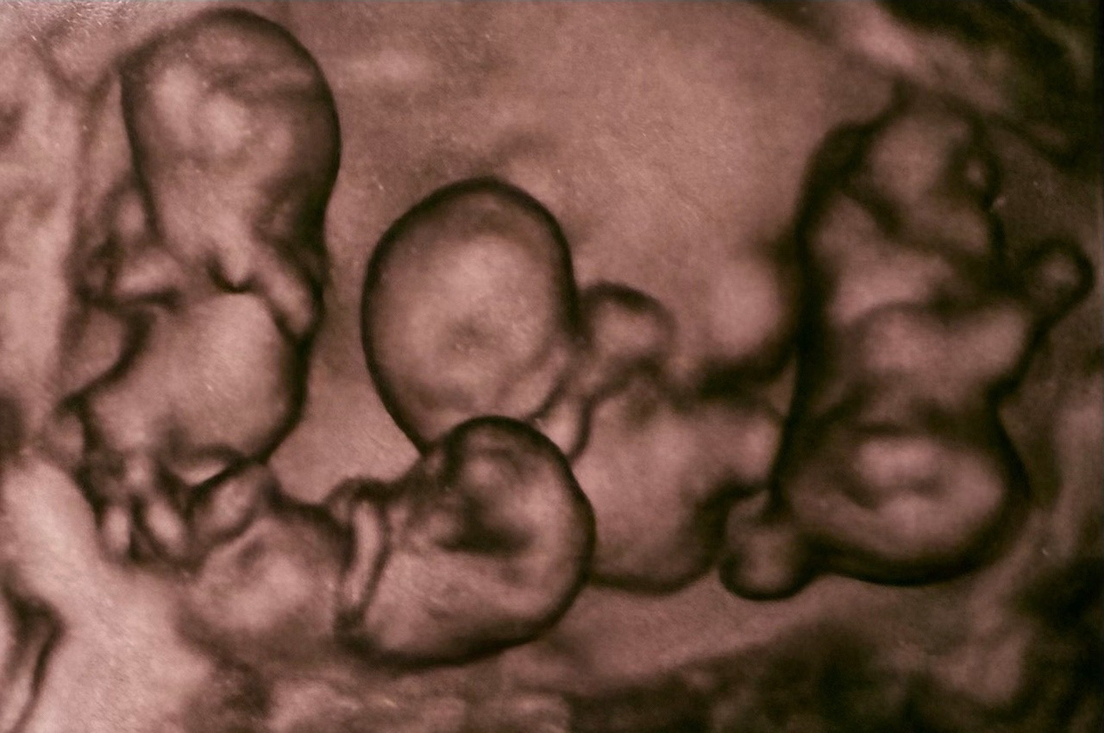

El 2 de abril nacieron en San Petersburgo unas cuatrillizas monocigóticas, es decir, cuatro bebés idénticas provenientes de un solo óvulo fecundado, un hecho sin precedentes en la historia de la medicina de Rusia, recogen este domingo medios locales.

El acontecimiento tuvo lugar en el hospital de maternidad Nº.17, de la ciudad rusa. Las cuatro bebés nacieron a las 32 semanas de gestación. De acuerdo con especialistas, este tipo de embarazo es extremadamente raro, ya que se estima que ocurre una vez cada 15,5 millones de partos.

Un equipo de obstetras, anestesiólogos y neonatólogos encabezados por el director del hospital realizó la compleja intervención, garantizando la seguridad de la madre y las recién nacidas. De acuerdo con la institución médica, las niñas presentaron condiciones de salud acordes a su edad gestacional, con pesos que oscilaron entre 1,36 y 1,64 kilogramos.